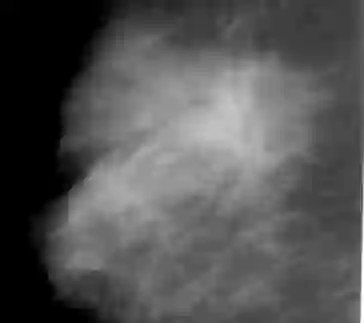

The deep learning technique has been shown to be effective in addressing several image analysis tasks within the computer-aided diagnosis scheme for mammography. The training of an efficacious deep learning model requires large amounts of data with sufficient diversity in terms of image style and quality. In particular, the diversity of image styles may be primarily attributed to the vendor factor. However, the collection of mammograms from large and diverse vendors is very expensive and sometimes impractical. Motivatedly, a novel contrastive learning method is developed to equip the deep learning models with better generalization capability. Specifically, the multi-style and multi-view unsupervised self-learning scheme is carried out to seek robust feature embedding against various vendor styles as a pre-trained model. Afterward, the pre-trained network is further fine-tuned to the downstream tasks, e.g., mass detection, matching, BI-RADS rating, and breast density classification. The proposed method has been extensively and rigorously evaluated with mammograms from various vendor-style domains and several public datasets. The experimental results suggest that the proposed domain generalization method can effectively improve the performance of four mammographic image tasks on data from either seen or unseen domains and outperform many state-of-the-art (SOTA) generalization methods.